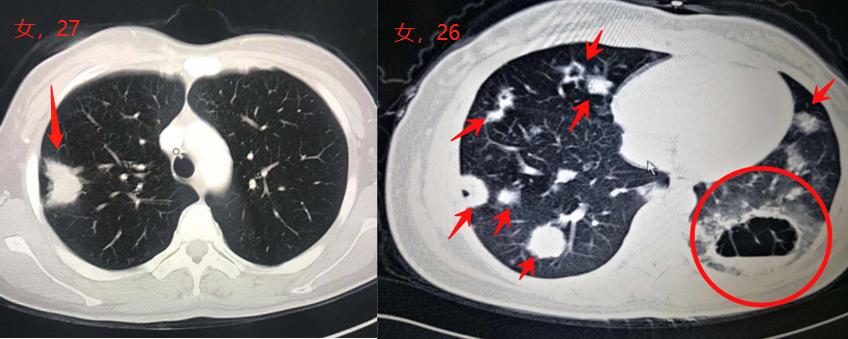

这是最近半年内遇到的两位年轻女士,都不到30岁,肺腺癌,左图的还有手术机会。

右图的女士才26岁,刚生完宝宝1个月,从怀孕5个月的时候开始间断咳嗽,有过一次咯血,来医院检查的时候就多发转移了……

这么年轻的病例实在难以防范,好在这种情况很少见!